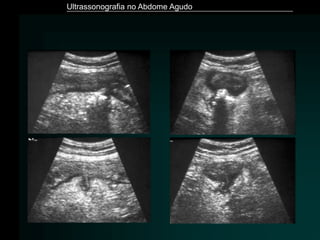

Apendicite Aguda

– Sinais ecográficos

» Apêndice com diâmetro ≥ 7 mm

» Espessamento das paredes

» Perda de definição das camadas

» Perda da compressibilidade

» Líquido intraluminal

» Hiperfluxo ao Doppler

» Apendicolito (30%)

» Halo hiperecóico

• inflamação da gordura periapendicular

» Líquido periapendicular

Ultrassonografia no Abdome Agudo

Rybkin. Radiol Clin N Am 45 (2007) 411–422

Apêndice Normal

Puylaert. Radiol Clin North Am. 2003 Nov;41(6):1227-42